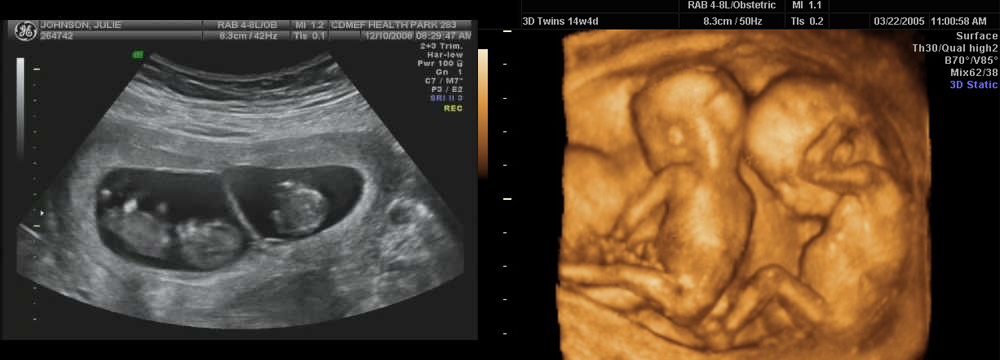

Фотографии и информация о многоплодной беременности на 12 неделях

Раздел: Фотоэссе